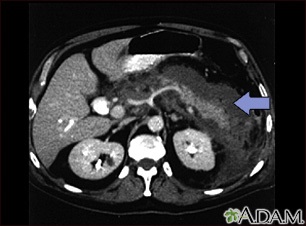

This upper abdominal CT scan shows inflammation and swelling of the pancreas caused by acute infection (pancreatitis).